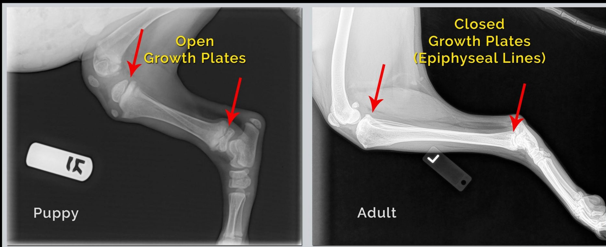

Describe pediatric patient radiography.

Growth plates are open, time of closure varies between joints. Cartilage is NOT visible on xrays.

Factors that affect closure time:

- Breed, nutrition, anatomical location etc.

- Hormonal effect

- Growth hormone, thyroid hormone, sex hormones, insulin.

- Individual variation

Describe mature patient radiography.

Epiphysis and diaphysis fused, physis closed.

- Different age in different bones

Dogs: usually all physes closed by age of 18 months.

Young castrated cats: physes open until age of 18 months, very often open until age of 2-3 years.

Physeal “scar” – thin horizontal radiopaque line in place of closed physis.

Pictured white line is a sort of “scar” from where the growth plate closed.